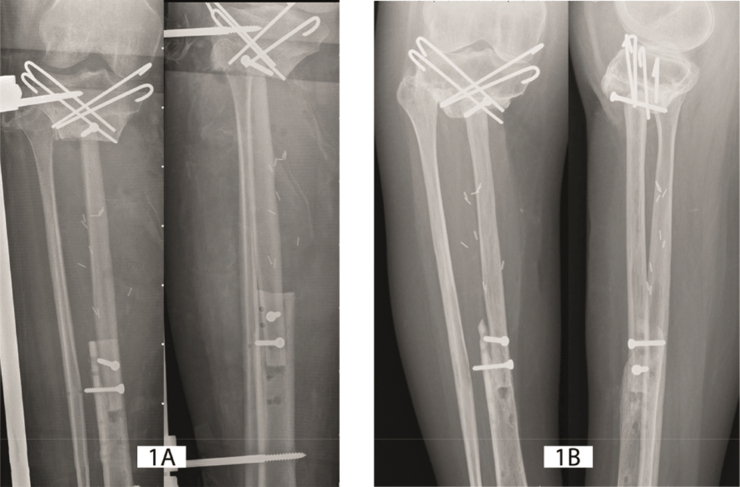

Results: When bony consolidation of the 33 cases were examined in detail, 4 different modes of flap hypertrophy were defined: type 0- absence of hypertrophy, type 1- limited hypertrophy, type 2- marked hypertrophy triggered by stress fracture, and type 3- massive hypertrophy enhanced by peripheral bone production.